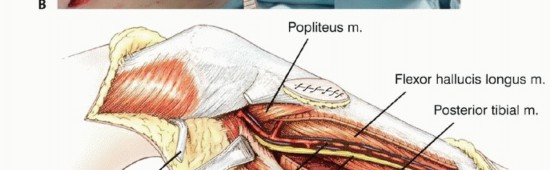

لفهم مدى تعقيد جراحة أورام قصبة الساق القريبة، من الضروري الإلمام بالتشريح الدقيق لهذه المنطقة. يشتمل استئصال قصبة الساق القريبة على إزالة ما بين نصف إلى ثلثي قصبة الساق، بالإضافة إلى جزء من جميع العضلات التي ترتكز عليها، والعضلة المأبضية بأكملها. كما يتضمن الاستئصال إزالة المفصل الظنبوبي الشظوي القريب خارج المفصل، مع الحرص الشديد على الحفاظ على العصب الشظوي، وهو أمر حيوي لوظيفة القدم.

من الضروري تقريباً ربط الشريان الظنبوبي الأمامي أثناء الاستئصال، بينما يجب تحديد الأوعية الأخرى بعناية قبل ربطها. تتميز العضلة المأبضية بكونها تغطي السطح الخلفي لقصبة الساق، مما يوفر حاجزاً ممتازاً بين امتداد الأنسجة الرخوة الخلفية من قصبة الساق والحزمة الوعائية العصبية للطرف السفلي. هذه الميزة التشريحية الفريدة والمحظوظة تختلف عما يحدث في عظم الفخذ البعيد، حيث يتم تغطية الجانب الخلفي فقط بالدهون المأبضية.

استكشاف الحفرة المأبضية والحزمة الوعائية

يجب استكشاف تفرع الشريان المأبضي مبكراً لتحديد ما إذا كان الورم قابلاً للجراحة، خاصة إذا كانت مكوناته في الأنسجة الرخوة تمتد خلفياً. إذا لم يكن هناك امتداد خلفي، يتم تعريض الفراغ المأبضي والتفرع عن طريق فصل العضلة التوأمية الإنسية وشق العضلة النعلية. يمكن تحديد الشريان المأبضي بسهولة وتتبعه بعيداً حول العضلة المأبضية. يجب توخي الحذر لتحديد وحماية جميع الفروع الوعائية الرئيسية.